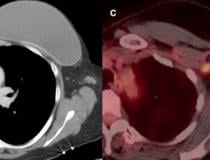

This photo gallery shows the variety of radiological presentations of COVID-19 (SARS-CoV-2) in medical imaging, including computed tomography (CT), radiograph X-rays, ultrasound, echocardiograms and magnetic resonance imaging (MRI). The radiology images show examples of typical COVID pneumonia in the lungs and the numerous complications the virus causes in the body in multiple organs, including the brain, kidneys, heart, abdomen and vascular system.

Ultrasound, especially hand-held ultrasound imaging devices, have become a primary imaging modality for novel coronavirus because of the ease to bag the device and sterilize it after use. CT and mobile X-ray systems are also used as front-line imaging systems for COVID-positive or suspected COVID patients.